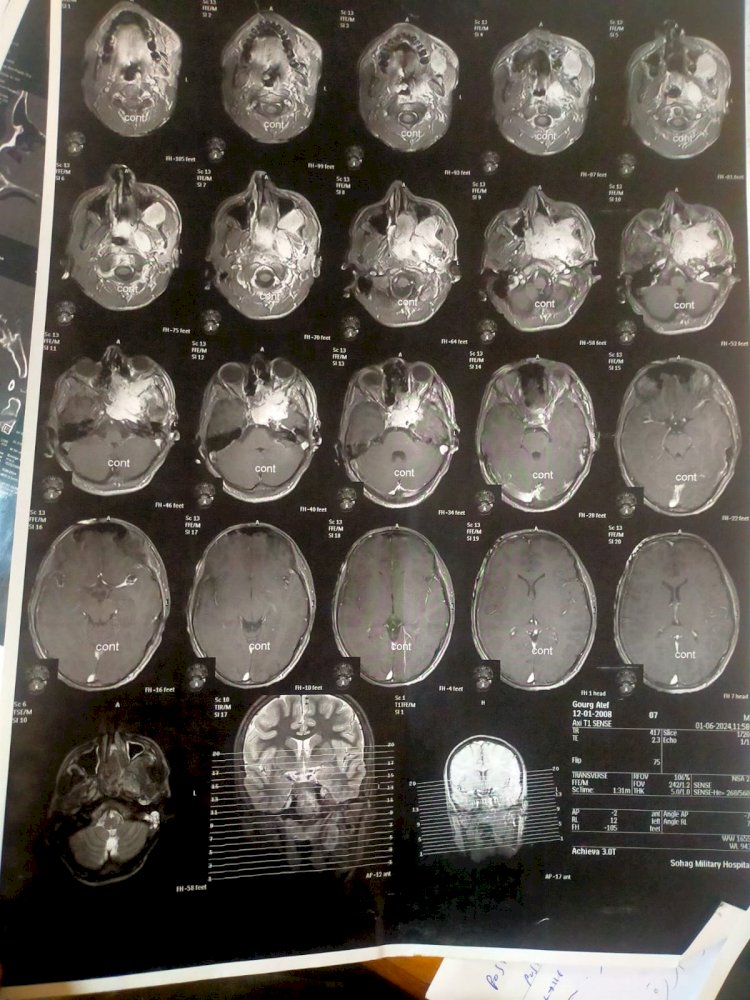

وقال الدكتور سمير عبدالمجيد مدير مستشفي الطوارئ بالحرم الجامعي الجديد، أن المريض وصل الي المستشفي بحالة انسداد الأنف وتاريخ مرضي لنوبات نزيف شديدة ومتكررة من الأنف كادت تودي بحياته، فعلي الفور تم إنهاء إجراءات دخول المريض بالقسم، وعمل الفحوصات المخبرية وشملت إجراء تحاليل دم وفصيلة دم وتجهيز ٣ أكياس دم ، وأشعة مقطعية ورنين بالصبغة، وأشعه مقطعية على الأنف والجيوب الأنفية بالصبغة، ورنين على المخ وقاع الجمجمة بالصبغة، وعقب الإنتهاء من التجهيزات اللازمة تم دخوله غرفة العمليات وخرج في حالة مستقرة.